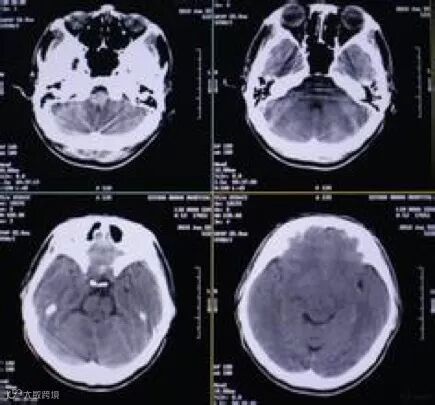

头颅CT的各个断层